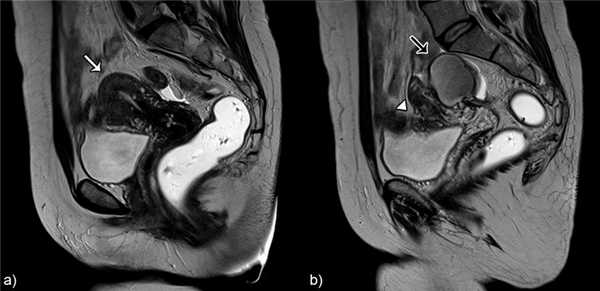

Лейомиомы присутствуют в почти половине случаев с аденомиозом матки.2. Глубокий тазовый эндометриоз (Рис.18)

Около одной трети молодых женщин с клиническим подозрением на глубокий инфильтративный эндометриоз на МРТ имеют признаки аденомиоза матки. Кроме того, тяжесть инфильтративного эндометриоза, кажется, коррелирует с аденомиозом.3. Полип эндометрия / гиперплазия эндометрия (Рис.19)

Было доказано, что аденомиоз в значительной степени связан с полипами эндометрия и шейки матки.![]()

Рис.17 Диффузный аденомиоз и лейомиомы: а) аксиальные T2 b) сагиттальные T2 взвешенные изображения, показывающие диффузное утолщение переходной зоны (белая стрелка) и множественные гипоинтенсивные массы, представленные лейомиомами (звездочки).

![]()

Рис.18 Аденомиоз и эндометриоз: а) и b) Саггитальные T2 взвешенные изображения, расширение переходной зоны с формированием плохо отграниченной области низкой интенсивности сигнала с мелкими гипериненсивными включениями - аденомиоз (белая стрелка); узел эндометриоза в стенке мочевого пузыря (наконечник стрелки); эндометриома в левом яичнике с T2 shading эффектом (черная стрелка).

Рис.19 Диффузный аденомиоз и полип эндометрия: а) и b) сагиттальные T2 с) корональный T1 3D FS с контрастом, плохо определенное утолщение переходной зоны (аденомиоз) и гипоинтенсивное узловое образование в полости матки, представленное небольшим полипом эндометрия (стрелки).